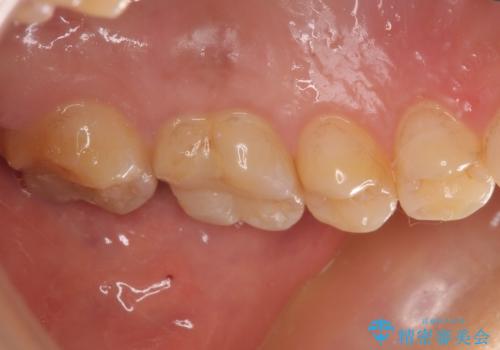

初回の根管治療を終えた2日後には膿の出口が消失し、咬んだときの不快な痛みもなくなりました。

PGAクラウンにしたことで咬み心地に全く違和感がなく、気にされていた審美面も、奥歯でありそれほど目立たないこともありますが、白金加金の色を気に入っていただけたので、患者様には大変満足していただけました。